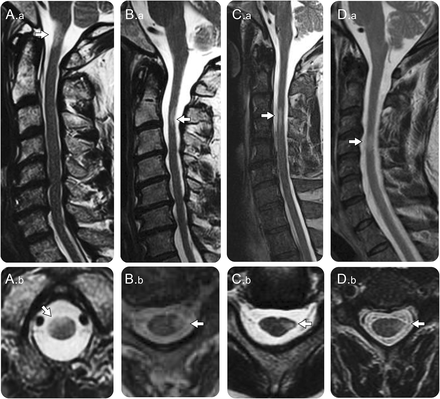

大脑和脊髓MRI发现进步的孤独的硬化病变中进行了总结表、有代表性的图片所示图1 - 3。28患者大脑、颈椎和胸椎磁共振成像;2患者颈脊髓损伤解释他们的症状有一个正常的大脑核磁共振但没有接受胸椎MRI。中位数时间从出现症状到核磁共振是63个月(范围15 - 343)。这MRI包括整个中枢神经系统(大脑、颈、胸线)59%确认任何新的病变了。单一解剖情况下只有一个病理损伤。

(A)一名52岁的男子与进步的上运动神经元的四肢瘫痪T2-hyperintense病变在cervico-medullary结(矢状图像。,箭头)位于正确的多轴向图像(左前绳。b,箭头)。(B)一名56岁男子与进步(face-sparing)痉挛性左轻偏瘫T2-hyperintense病变上颈绳在矢状图像(B。一个箭头)位于左边侧列在轴向图像(B。b, b与脊髓萎缩(箭头)。和反方向)。(C) 68岁的男子与激进的左派(face-sparing)轻偏瘫由于T2-hyperintense病变上颈绳在矢状图像(C。一个箭头);在轴向图像,病变在左边侧列与失去正常的圆形脊髓边缘表明焦萎缩(C。b,箭头)。(D) 57岁男子提出亚急性发作的左(face-sparing)轻偏瘫和随后的进步左轻偏瘫与T2-hyperintense病变mid-cervical绳在矢状图像(D。,涉及左边侧列在轴向的箭头)图像(D灶状萎缩。b,箭头)。

孤独的中枢神经系统脱髓鞘病变通常位于颈脊髓或cervico-medullary结(表,图1)。脊髓病变都少于3椎段的长度。局部病灶萎缩与损失的圆形外观的脊髓轴向图像(图1中,B。b, C。b, D.b)是目前在初始成像或开发时间(图2)在21个26(81%)和足够的轴向序列可用;在2例,萎缩导致苹果的外观核心病变(图2 e)与下肢轻瘫或四肢瘫痪。双边病变包括髓金字塔或cervico-medullary结(图3 b)与四肢瘫痪。

孤独的脊髓病变的平均宽度是5.5×4毫米(范围出)和平均长度是18毫米(范围7-52)。2 27例(7%),钆增强孤独的脊髓损伤的初始图像,随后解决(图2)。非特异性脑白质MRI T2 hyperintensities共存8例(27%)。